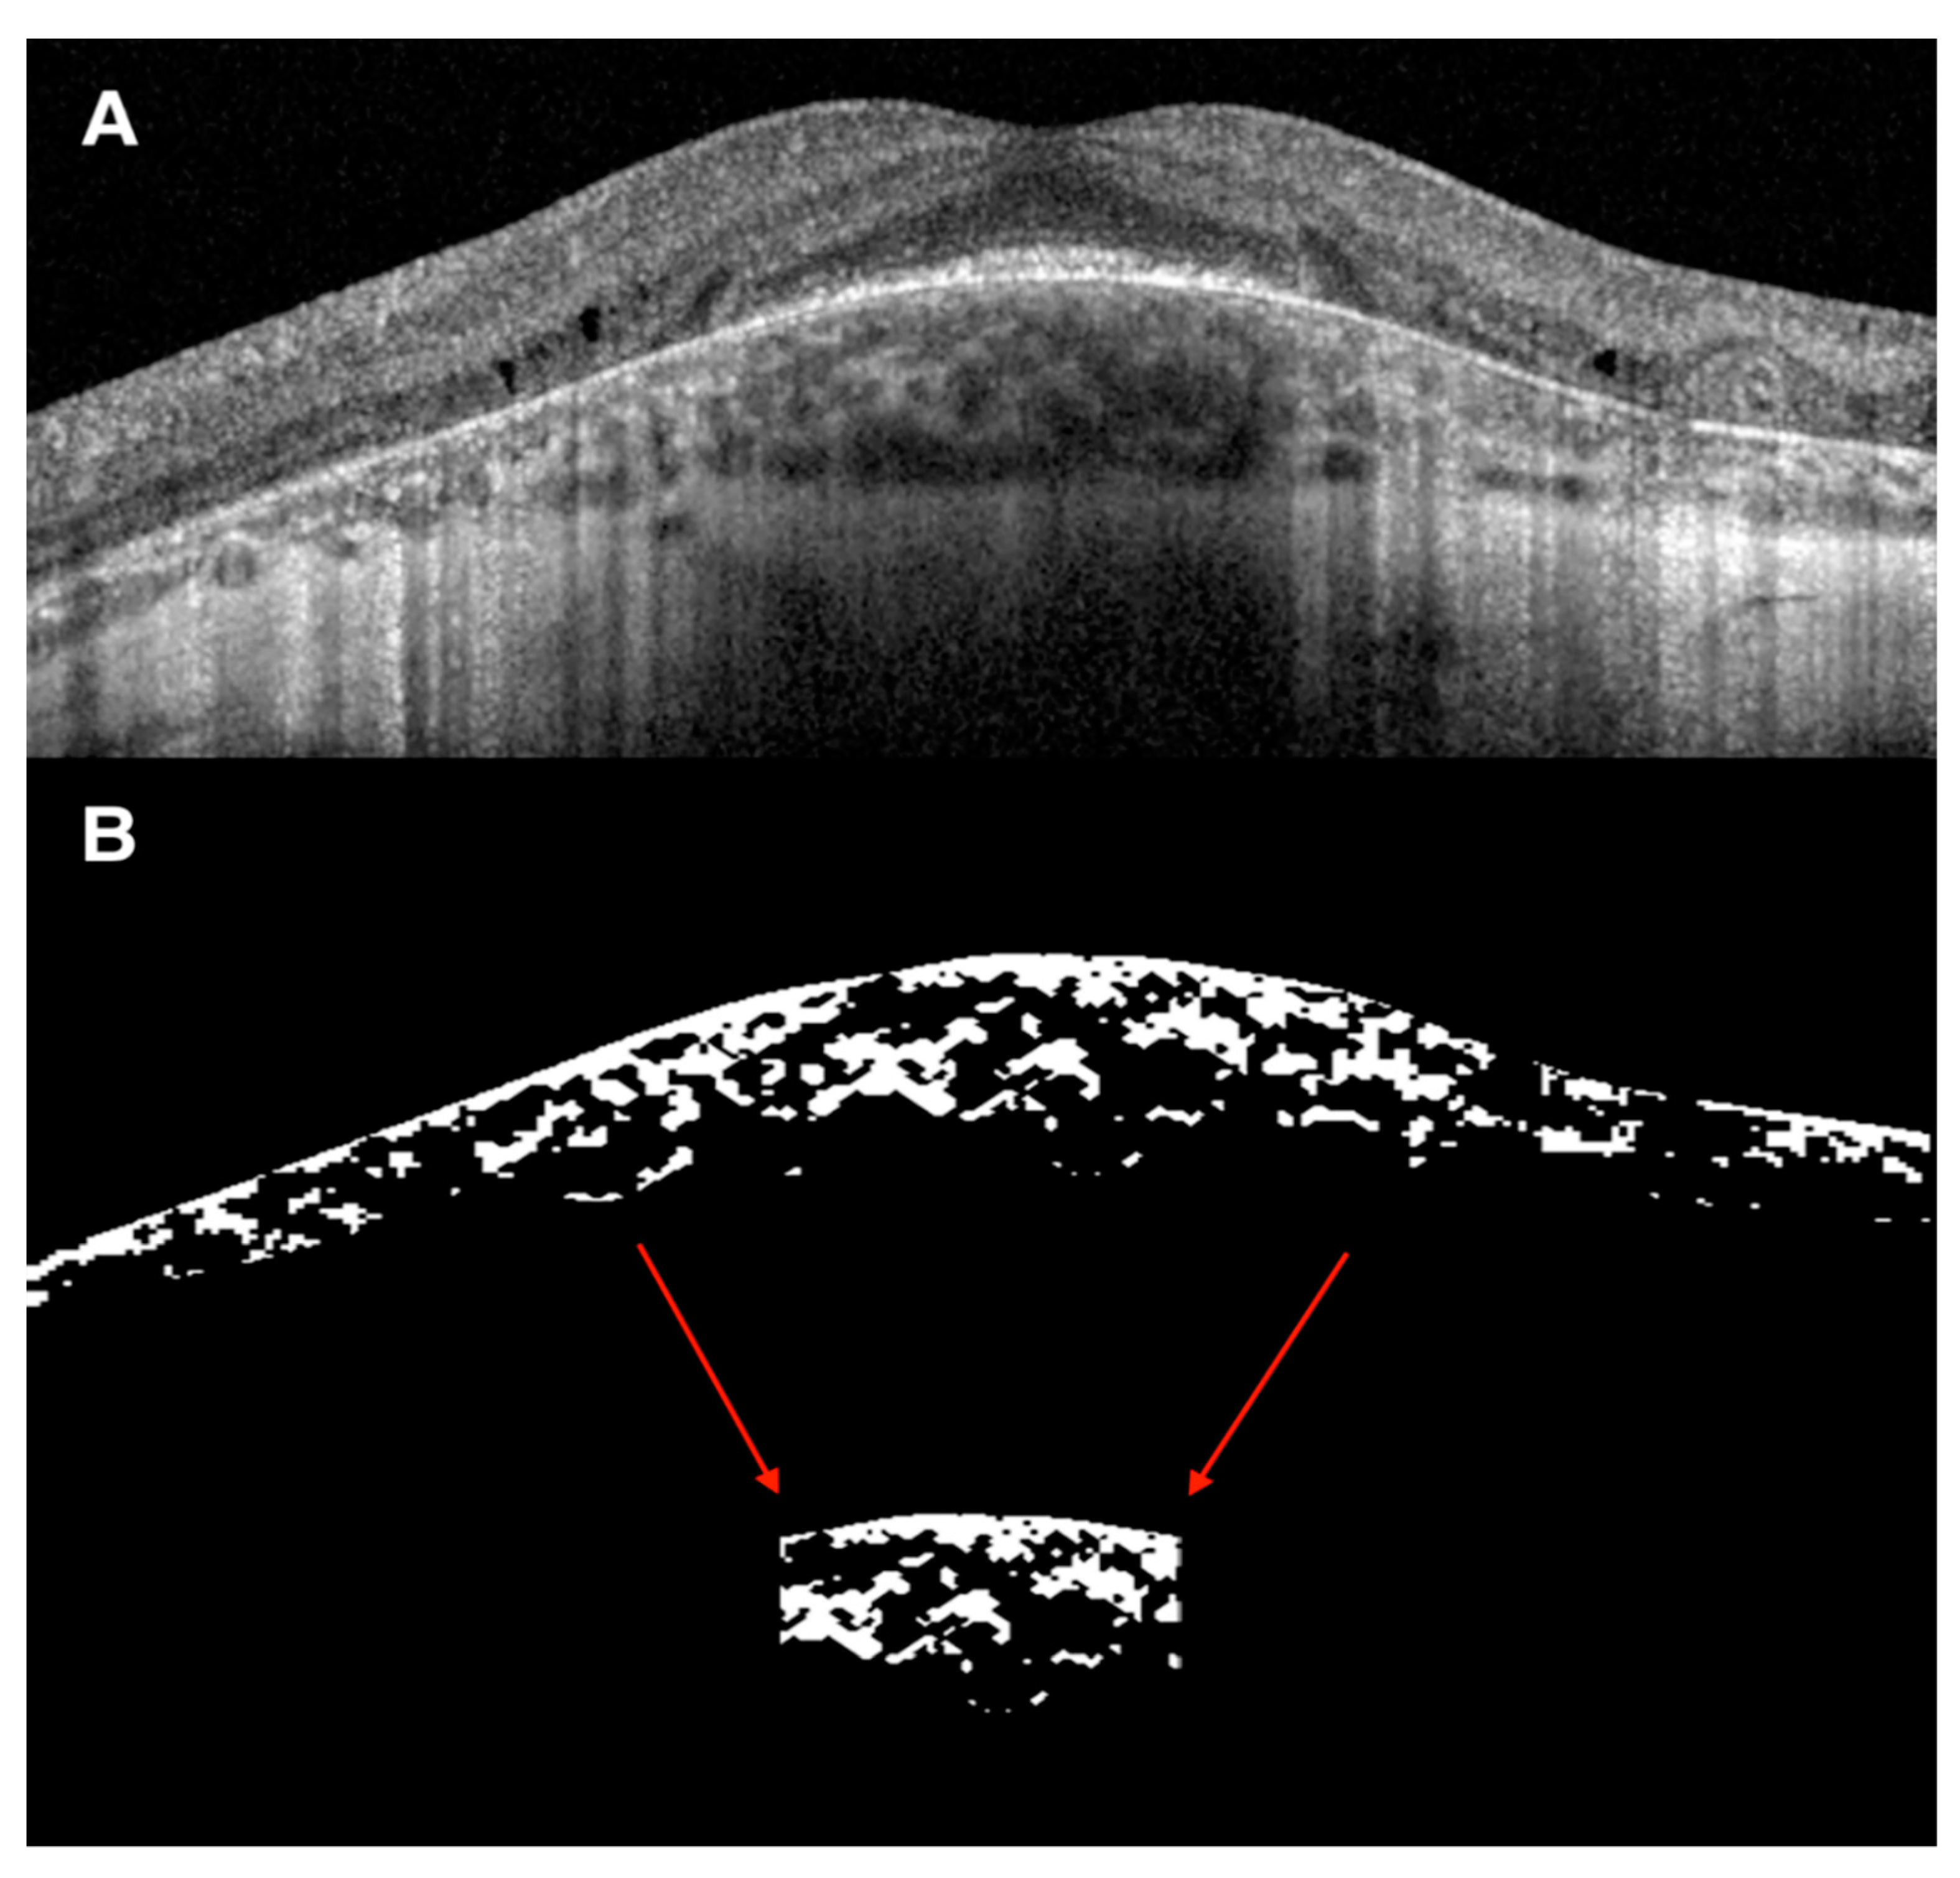

2.2. OCT Analysis of the Retina and Choroid